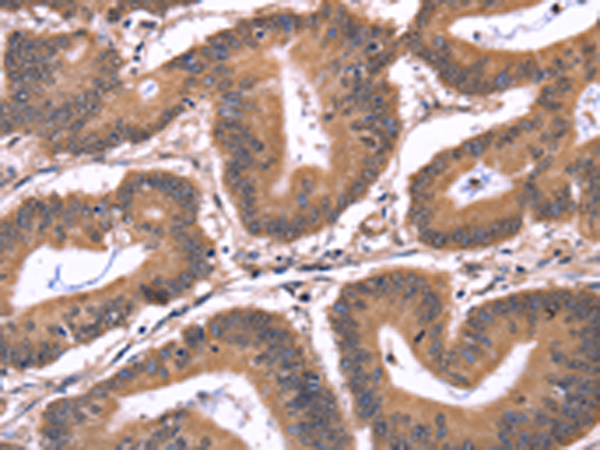

分类: 科研抗体货号: P08183别名: COT应用: WB,IHC反应种属: Human, Mouse, Rat